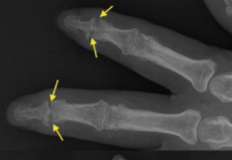

Psoriatic Arthritis

Pencil in cup deformity

Sausage Digits (nail changes)

Sausage Digits